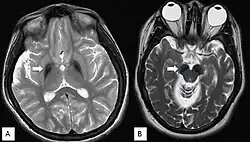

T2-gewichtete MRT-Sequenzen, die Globus-pallidus-Hypointensität (A) und Hypointensität der Substantia nigra (B) zeigen (Pfeile). Bei BPAN ist die Substantia nigra meist hypointensiver als der Globus pallidus, was auf einen höheren Eisengehalt hinweist.[9]

Da die Symptome meist unspezifisch sind, ist eine gesicherte Diagnose nur über bildgebende Verfahren und genetische Sequenzierung möglich. Im fortgeschrittenen Stadium sind mittels Magnetresonanztomographie Veränderungen in der Substantia nigra sowie im Globus pallidus erkennbar, die durch die Anlagerung von Eisen entstehen.[9][25] Frühe Anzeichen vor dem Auftreten von nachweisbaren Eisenablagerungen könnten ein Anschwellen der Substantia nigra sowie eine Hyperintensität in einer T2-gewichteten MRT-Aufnahme des Nucleus dentatus sein.[26] Letztendlich kann die Diagnose jedoch nur durch die Identifizierung der Mutation des WDR45-Gens abgesichert werden. Zur Diagnose der häufig auftretenden Epilepsie sind EEGs angezeigt.